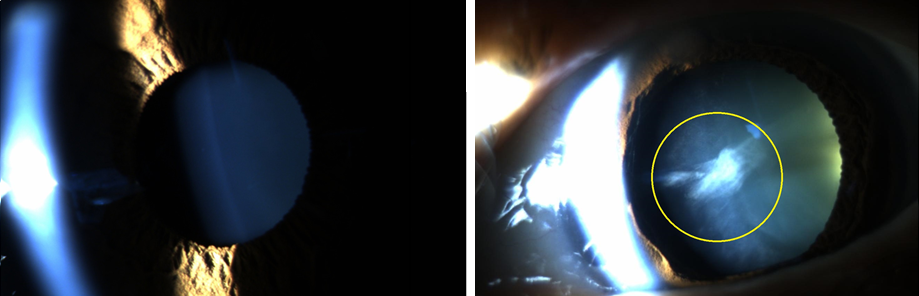

백내장인 눈과 정상안과 비교해보면 유관상으로도 큰 차이가 있음을 확인해볼 수 있습니다.

아래에 보시는 왼쪽 사진은 백내장 없는 일눈, 오른쪽은 백내장 수술 전 검사사진입니다.

세극등 검사에서 수정체가 깨끗한 정상안은 까맣게 보이는데, 백내장인 경우 아래 표시한 부분처럼 하얗게 보이게 됩니다.